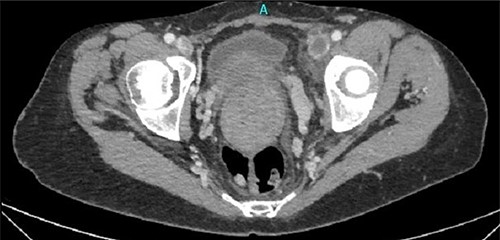

One month later, after vascular consultation, a chest and pelvis computed tomography angiography was performed and a huge mass originating from the uterine wall was revealed (26 cm in diameter) (Fig. 1). The mass compressed the surrounding organs, especially IVC (Fig. 2). Furthermore, thrombosis of left femoral and external and common iliac veins, as well as infrarenal IVC patency (without clarification of IVC thrombosis), was detected. The common, internal and external right iliac veins were patent, and no PE was detected.

A huge mass originating from the uterine wall was revealed after pelvis CTA.

Thrombosis of left femoral and external and common iliac veins.